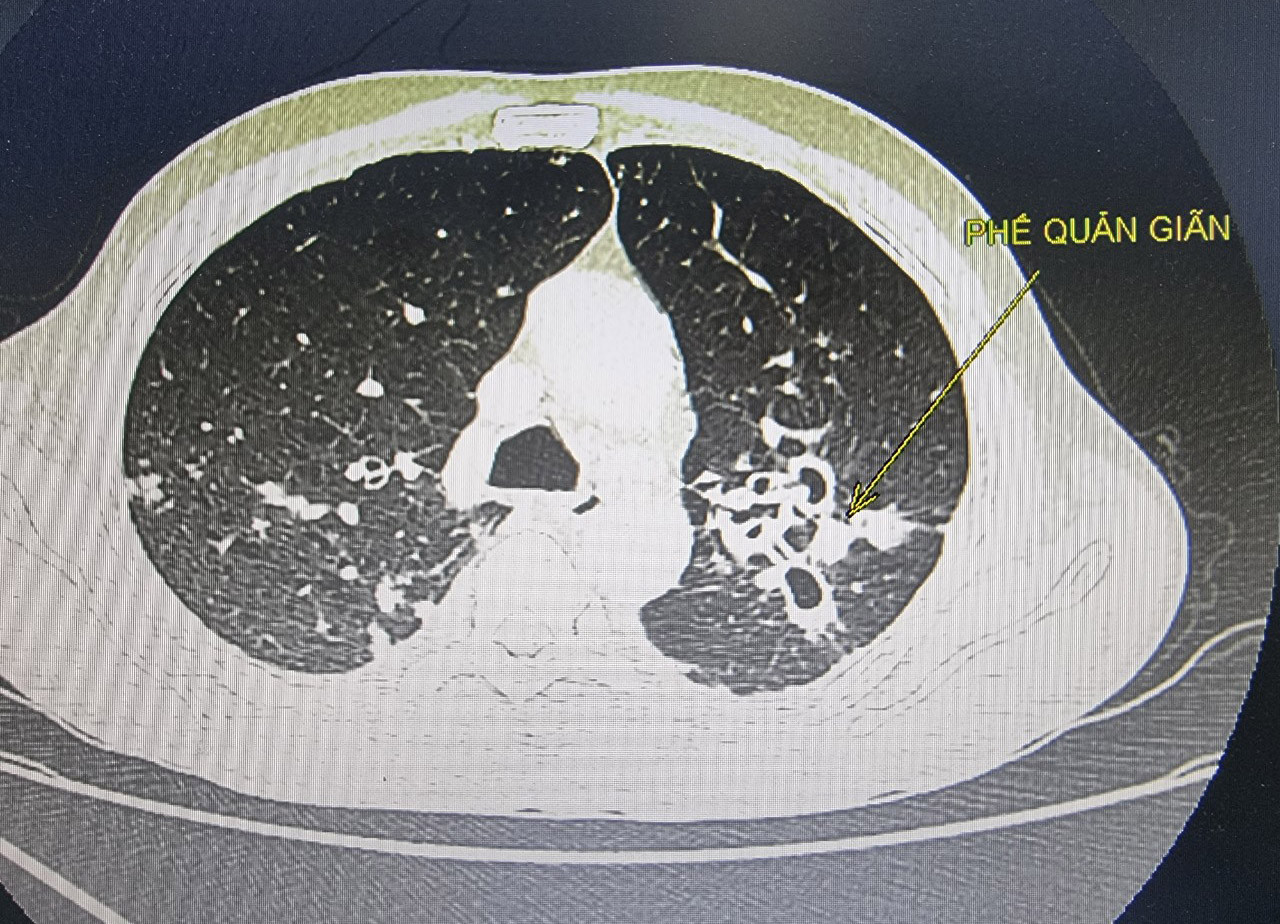

Kết quả chụp cắt lớp vi tính cho thấy bệnh nhân bị giãn phế quản hai bên phổi, động mạch phế quản hai bên giãn ngoằn ngoèo, có luồng thông với động mạch phổi. Các bác sĩ đã hội chẩn can thiệp nút động mạch phế quản cầm máu cho bệnh nhân.